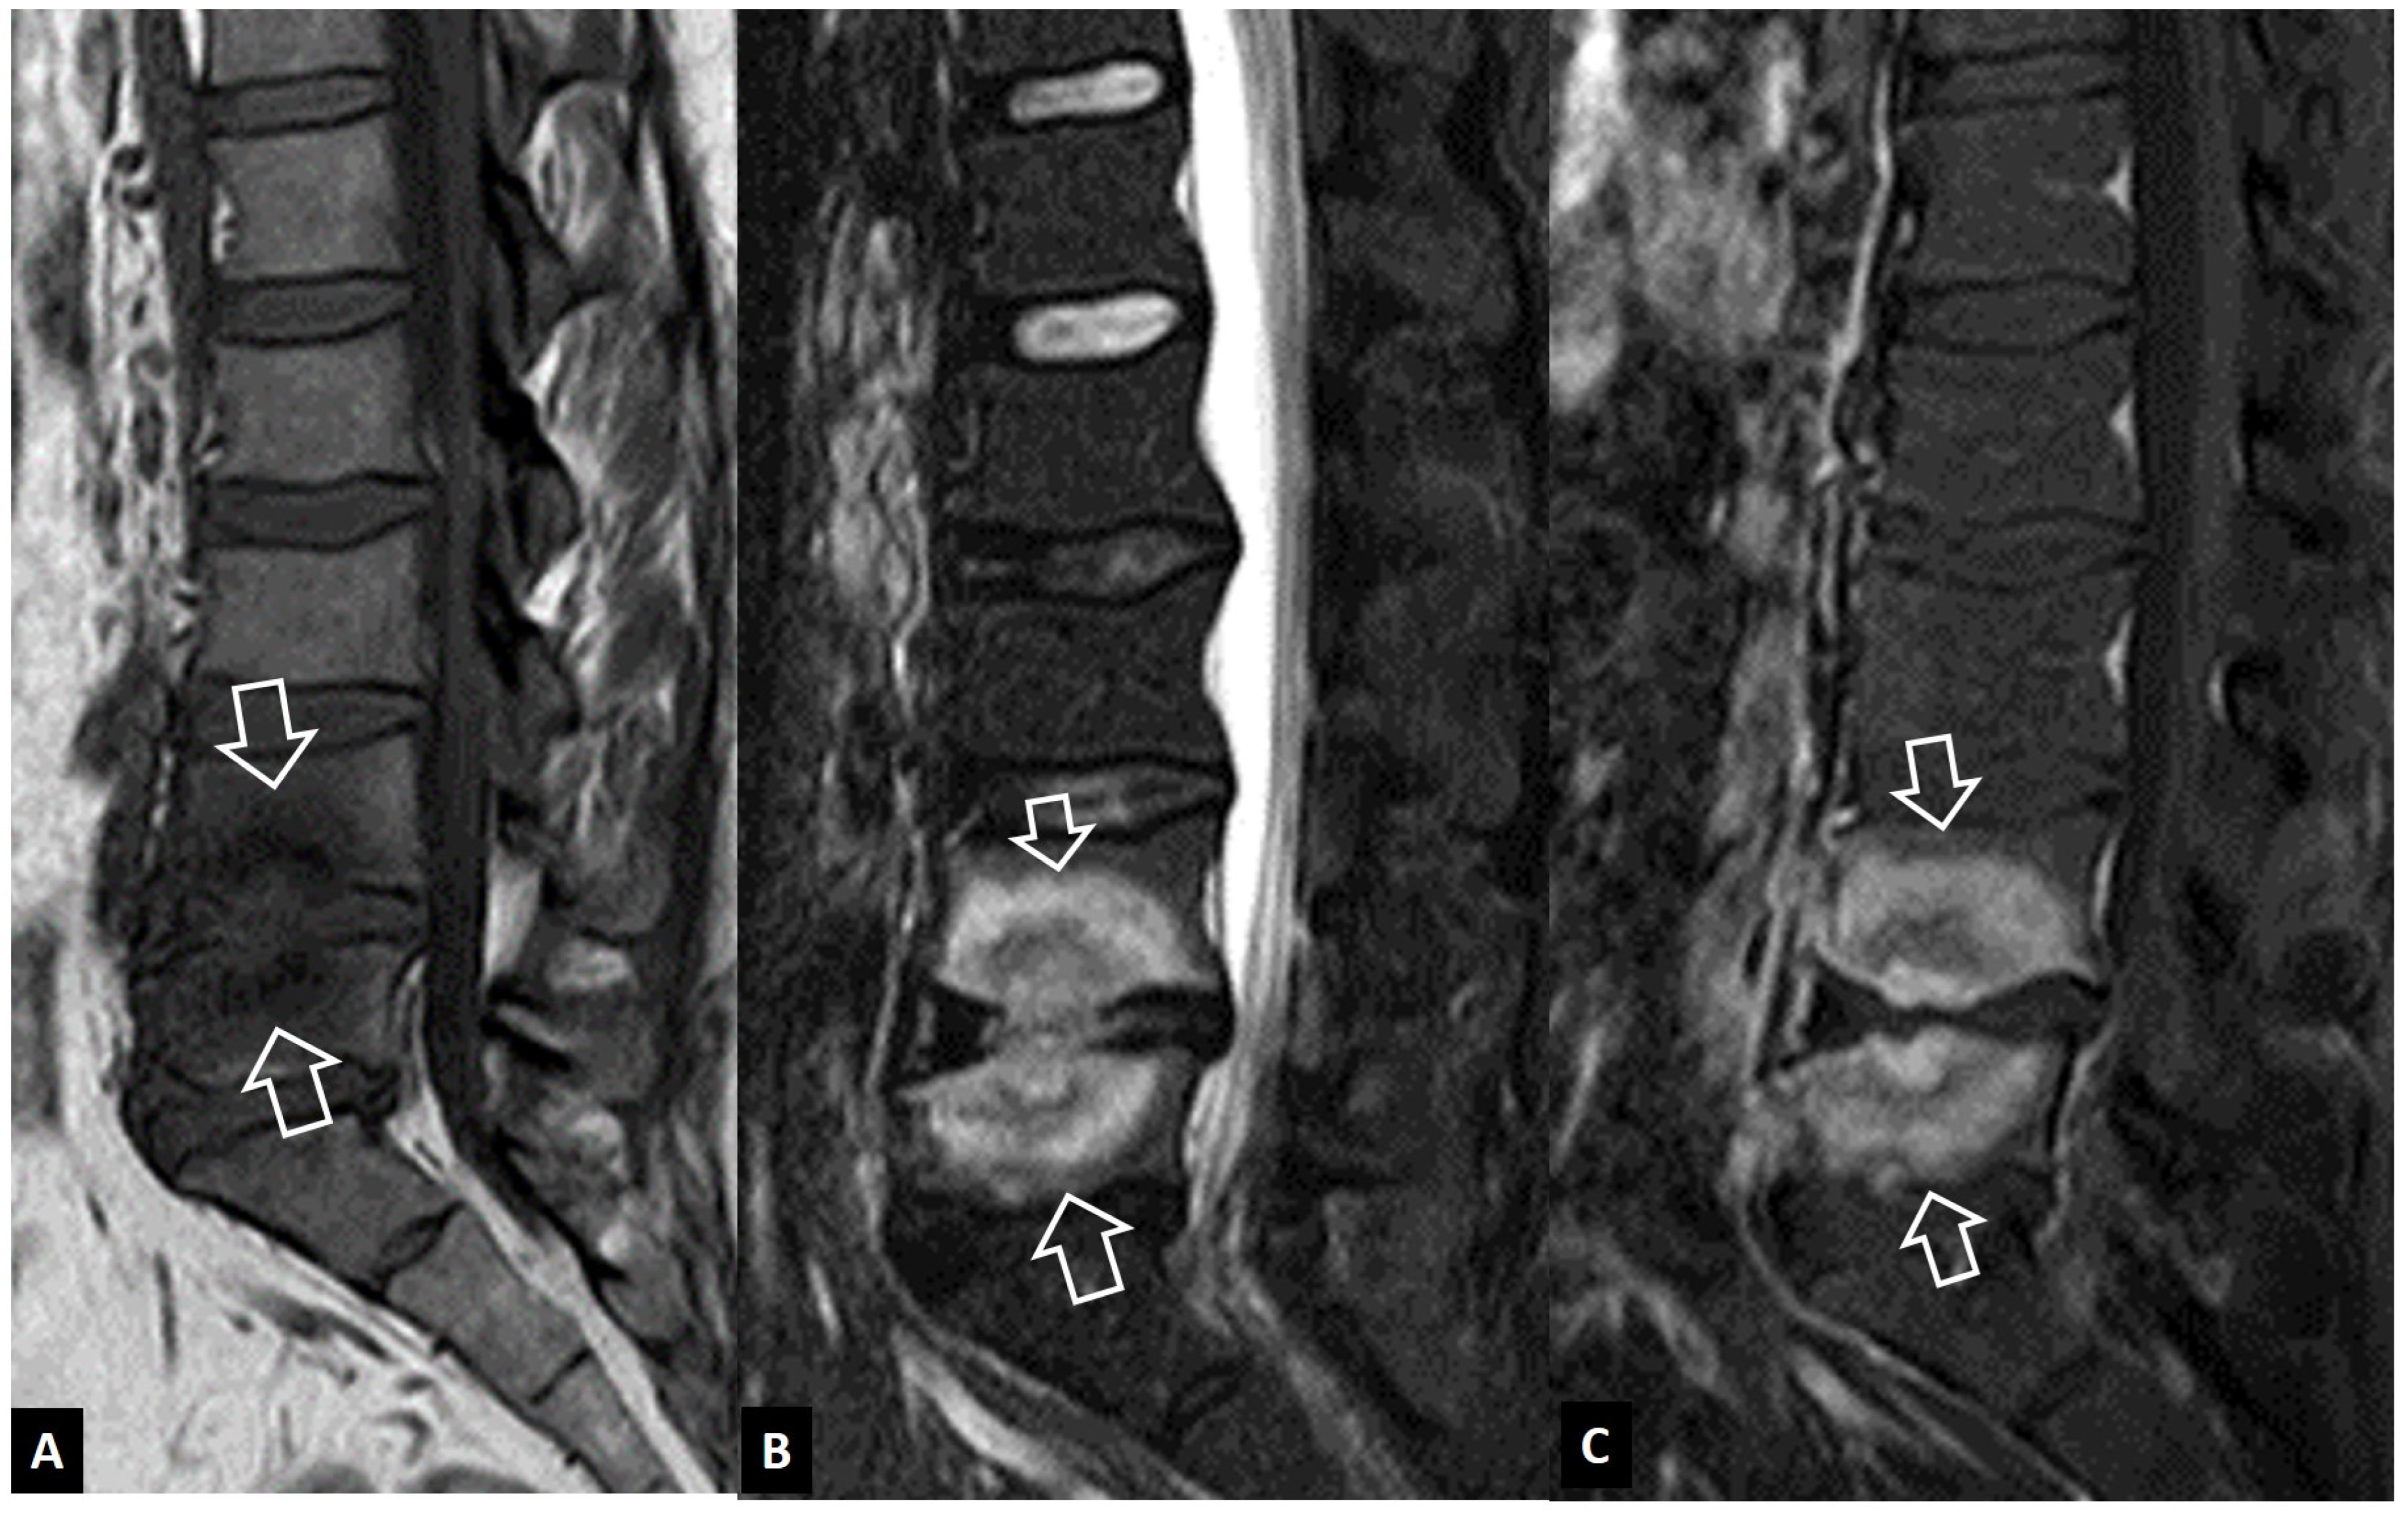

2.1.4. Destructive Spondyloarthropathy

2.1.5. Crystal Deposition